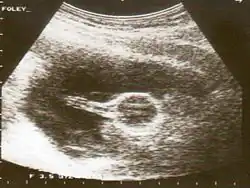

В рентгенологии катетер Фолея применяется при проведении гистеросальпингографии — диагностики с помощью рентгеновских лучей состояния фаллопиевых труб и внутренней полости матки. Двухходовой катетер Фолея диаметром 4,7—5 мм вводится внутриматочно, удерживающий баллон раздувается в объёме 2—3 мл, после чего через дренажный порт в матку вводится рентгеноконтрастный препарат. Рентгеновские снимки выполняются сразу после введения, затем через 10—15 минут, затем, если в этом есть надобность, через 24 часа[4].

Использование катетера Фолея при гистеросальпингографии имеет ряд преимуществ по сравнению с традиционными методами: в частности, обеспечивается полная герметизация матки, а проведение процедуры является менее болезненным[4].